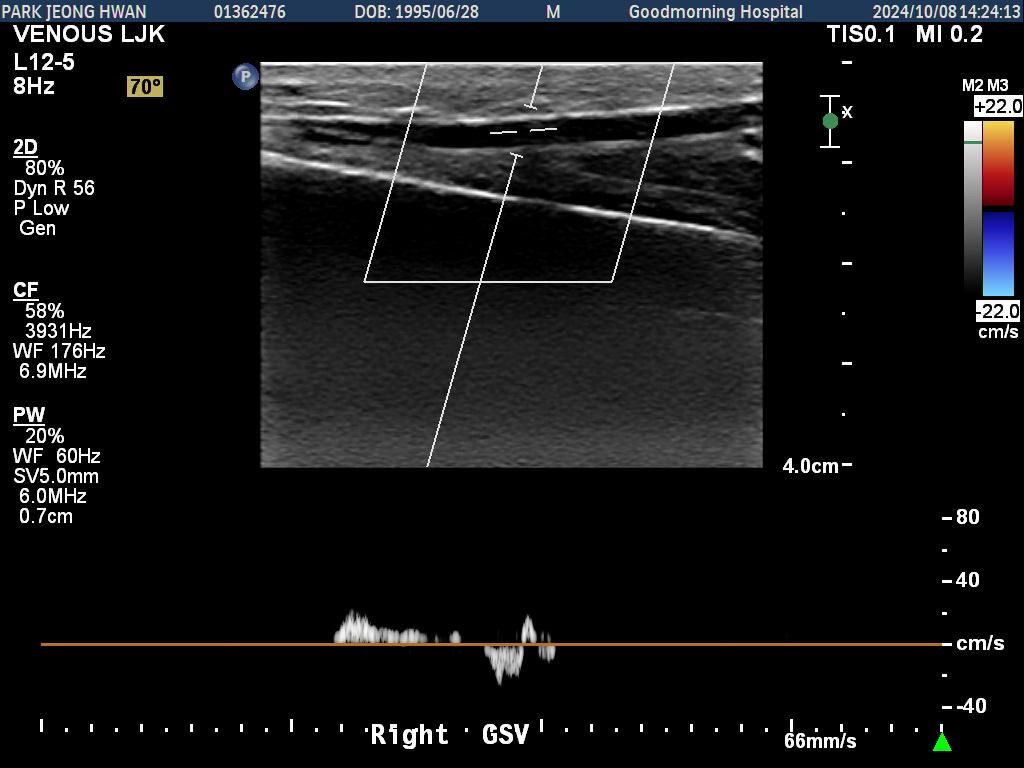

오른쪽 다리만 찍은 거구요. 종아리에서 사타구니까지 부분별로 찍었습니다.......................

• 1번 째 사진

• 2번 째 사진